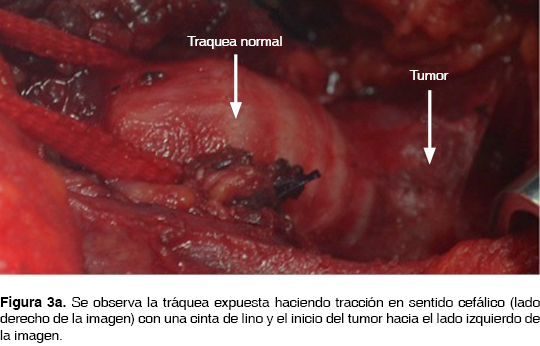

El abordaje cervical para la resección fue planeado, la paciente permaneció en decúbito dorsal para realizar la broncoscopia preoperatoria, se administró anestesia general balanceada con intubación orotraqueal, con cánula número 6 Fr., se colocó sonda esofágica 20 Fr. Se colocó con hiperextensión cervical. La disección fue a través de la línea media del cuello, el istmo se seccionó del tiroides para exponer la tráquea. La tráquea fue disecada hasta la carina principal para facilitar la movilización del segmento a resecar, se colocaron puntos de sutura distal y proximal al tumor para poder traccionar y manipular la tráquea, dejando el espacio suficiente para realizar la anastomosis. La tráquea fue cortada distalmente, la cánula orotraqueal retirada previa colocación de una sutura en el orificio de Murphy para facilitar la recolocación de la cánula después de haber realizado la anastomosis en la cara posterior; se cortó la tráquea en la parte proximal abarcando la totalidad del tumor (figura 3a, 3b), acto seguido fueron cortados bordes para enviarlos al estudio histopatológico transoperatorio. Para la ventilación cruzada por el campo quirúrgico, se utilizó una segunda cánula traqueal número 7.5 Fr., canulando la tráquea distal. El reporte histológico fue: bordes libres de tumor. Para realizar la anastomosis traqueal se utilizaron puntos simples con sutura absorbible 3-0; después de anudar los puntos en la pars flácida se avanzó la cánula orotraqueal una vez retirada la segunda cánula. Finalmente fue concluida la anastomosis, verificada la ausencia de fuga aérea y realizada la hemostasia; se afrontaron los tejidos y se colocó un punto de sutura del mentón al tórax para la flexión cervical forzada durante seis días. Al segundo día posquirúrgico se movilizó fuera de cama. La paciente fue egresada al séptimo día posquirúgico y valorada por el Servicio de Oncología quien decidió no otorgar ninguna terapia adyuvante.